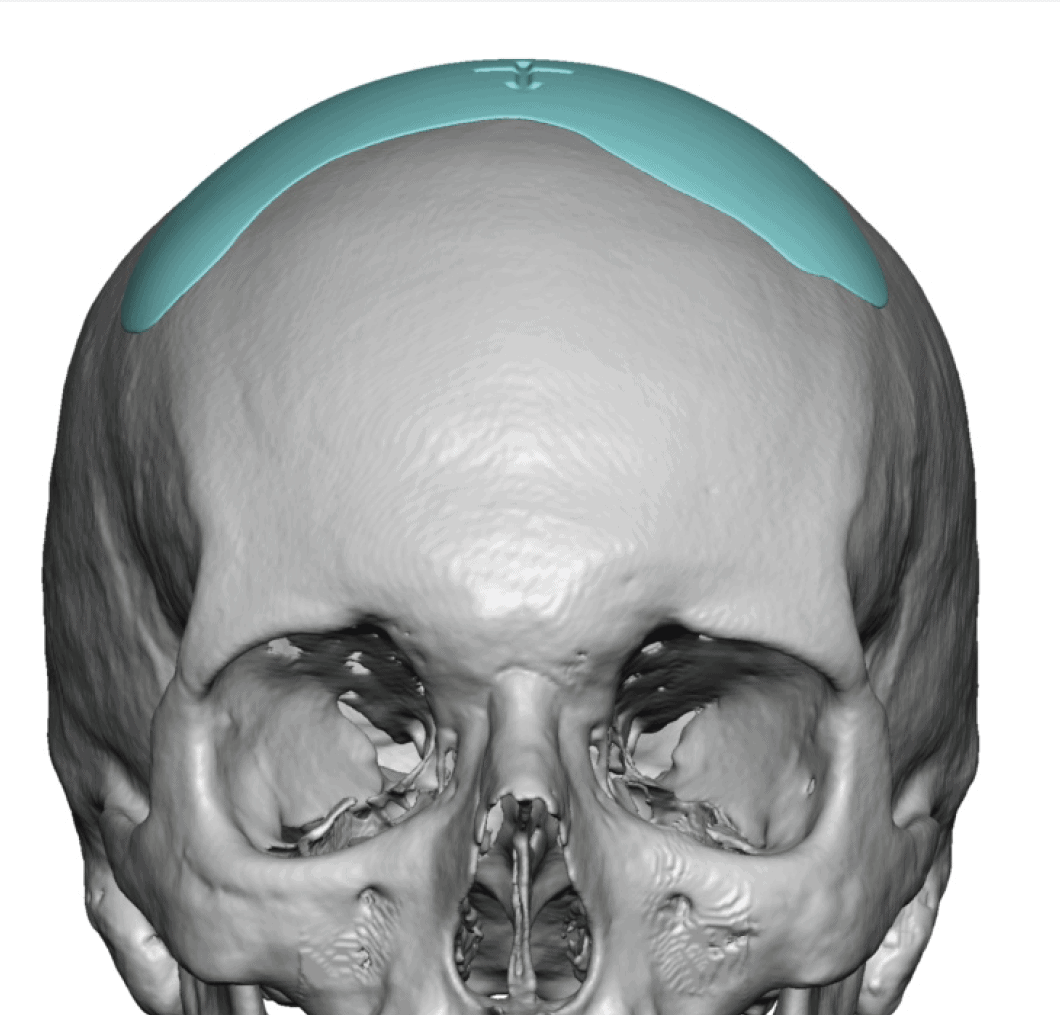

Patient 28

Desire for rounder shape to the top of the head from a congenital parasagittal deficiency skull shape.

Custom skull implant designed to fill in the parasagittal deficiencies.

Desire for rounder shape to the top of the head from a congenital parasagittal deficiency skull shape.

Custom skull implant designed to fill in the parasagittal deficiencies.